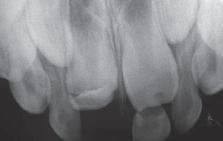

Quatre ans plus tard, l'examen radiographique a révélé des signes d'altération du germe de l'incisive centrale supérieure droite permanente (ill. 3), et les parents ont été informés des altérations morphologiques dans la dent permanente.

Ill. 3 : Examen radiographique 4 ans après le traumatisme dentaire, montrant des signes d'altération du germe de l'incisive centrale supérieure droite permanente.